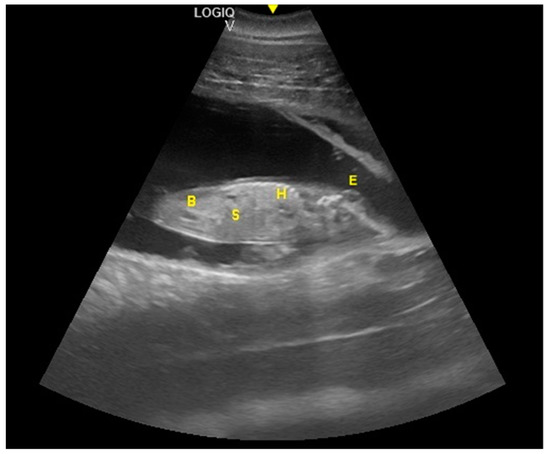

- Ivančič, M.; Gomez, F.M.; Musser, W.B.; Barratclough, A.; Meegan, J.M.; Waitt, S.M.; Llerenas, A.C.; Jensen, E.C.; Smith, C.R. Ultrasonographic findings associated with normal pregnancy and fetal well-being in the bottlenose dolphin (Tursiops truncatus). Vet. Radiol. Ultrasound 2020, 2020, 1–12. [Google Scholar]

- Thewisen, J.G.M.; Heyning, J.E. Embryogenesis and development in Stenella atenuatta and other cetaceans. In Reproductive Biology and Phylogeny in Cetacea, Whales, Dolphins and Porpoises; Miller, D.L., Ed.; Science Publishers: Enflield, NH, USA, 2007; pp. 307–330. [Google Scholar]

- Reidenberg, J.S.; Laitman, J.T. Prenatal development in cetaceans. In Encyclopedia of Marine Mammals, 2nd ed.; Perrin, W.F., Würsig, B., Thewissen, J.G.M., Eds.; Academic Press: San Diego, CA, USA, 2009; pp. 220–230. [Google Scholar]

- Cozzi, B.; Huggenberger, S.; Oelschläger, H. Anatomy of Dolphins: Insights into Body Structure and Function; Academic Press: London, UK, 2017; pp. 1–438. [Google Scholar]

- Sterba, O.; Klima, M.; Schildger, B. Embryology of dolphins. Staging and ageing of embryos and fetuses of some cetaceans. Adv. Anat. Embryol. Cell Biol. 2000, 157, 1–133. [Google Scholar]